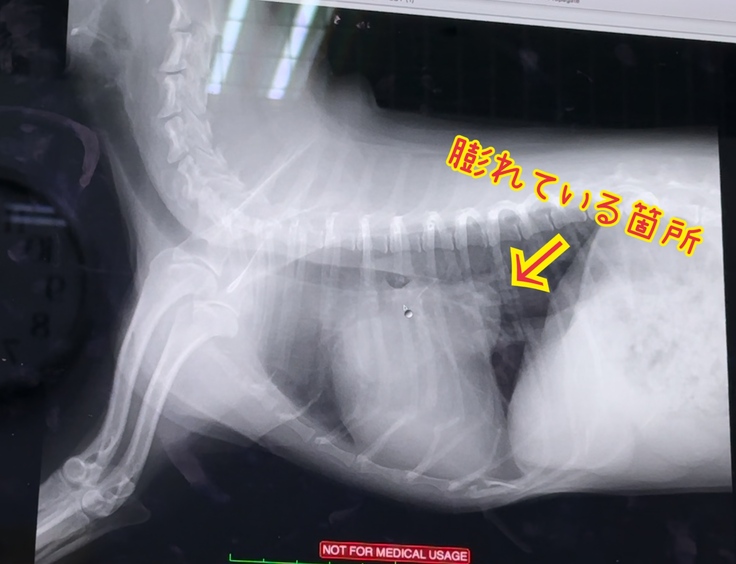

3ヶ月検診では左心房の膨らみが大きくなっており…

そこは、悪化はありませんでしたが

良くもなっていませんでした…